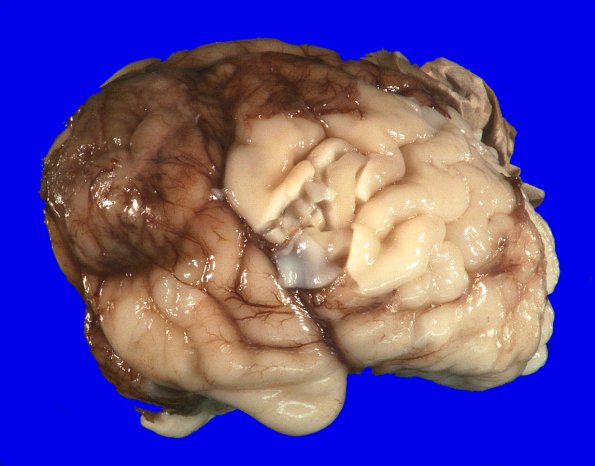

At autopsy the weight of the unfixed brain is 174 g (normal for age = 163 g). The superior occipital lobe abuts the encephalocele and is deformed and vascularized but only partially protrudes into the encephalocele